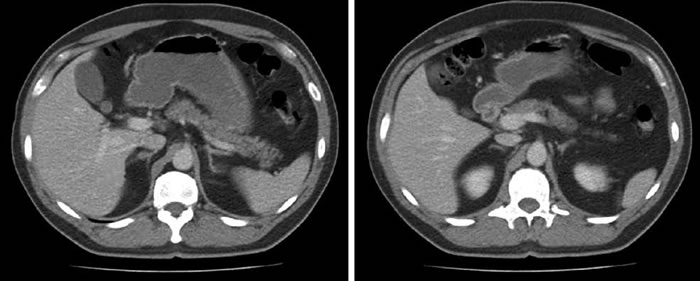

Hombre de 43 anos con antecedente de HTA, diagnosticada 3 anos antes, en tratamiento con Valsartan, Hidroclorotiazida y Carvedilol. No tenia antecedentes personales ni familiares de importancia. Se derivo a Endocrinologia por HTA de dificil manejo, con sospecha de hiperaldosteronismo. El paciente no referia sintomas respecto de cambio de peso, edema, episodios de taquicardia o hipertension, cefalea, palpitaciones, ni temblor de extremidades. En los examenes destacaba: Aldosterona plasmatica: 27,2 ng/dL; ARP: 0,5 ng/mL/h; AP/ARP 54,4; sodio 142 mEq/L; potasio 3.8 mEq/L; creatinina 0.94 mg/dL. Ecografia doppler renal normal. Dada la gravedad de la hipertension no se hizo prueba confirmatoria, por considerar que la administracion de fludrocortisona o la infusion salina eran potencialmente peligrosas. La TAC de abdomen mostro un nodulo unico de la corteza suprarrenal derecha de 11 x 5 mm (Fig. 2). Al examen fisico presentaba buen estado general con indice de masa corporal de 29, presion arterial 170/110 mmHg (en tratamiento). Para completar el estudio se realizo un CVS con infusion de ACTH (50 μg/h), que concluyo hallazgos compatibles con adenoma suprarrenal derecho secretor de aldosterona, y supresion de la glandula suprarrenal izquierda (Tabla 1b). Se inicio tratamiento preparatorio con Espironolactona, para luego efectuar suprarrenalectomia derecha por via laparoscopica. En el control medico 3 meses despues de operado, el paciente estaba en buenas condiciones generales, asintomatico, sin terapia antihipertensiva, con presion arterial de 120/80 mmHg y con valores normales de renina y aldosterona.

Tabla 1b. Resultado del CVS del caso clínico 2, que muestra lateralización a derecha de la secreción de aldosterona.

Los dos casos clínicos presentados ilustran la importancia del CVS para aclarar el diagnóstico etiológico del HAP. En el primer caso, las imágenes de la TAC mostraban compromiso bilateral pero con un nódulo predominante en el lado izquierdo, que no se correspondía funcionalmente con lo obtenido en el cateterismo venoso que demostraba lateralización a derecha. En el segundo caso, el paciente tenía un nódulo suprarrenal derecho de 11 mm, con correspondencia funcional, ya que lateralizaba al mismo lado en el CVS, permitiendo efectuar una suprarrenalectomía derecha exitosa.

Estos resultados son concordantes con casuísticas que demuestran que la TAC sólo tiene, en el mejor de los casos, una sensibilidad de 78% y una especificidad de 75% para determinar lateralización7,9. Las limitaciones de la TAC son más notorias en pacientes mayores de 40 años, por la mayor frecuencia de incidentalomas suprarrenales en ese grupo etario con respecto a individuos más jóvenes. También el examen está limitado cuando se sospecha bilateralidad, como ocurrió en uno de nuestros pacientes (Caso 1).